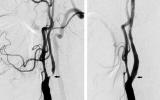

[제주건강보고서] [제주, 제주인의 건강보고서 Ⅷ 건강다이어리] (153)경동맥 협착증

[한라일보] 협착 심하면 뇌혈류 감소·뇌동맥 폐색으로 뇌경색 유발까지관 삽입으로 혈관 확장하는 ‘스텐트 삽입술’ 최근 빈도 늘어 경동맥은 총경동맥, 내경동맥, 외경동맥으로 구분된다. 총…